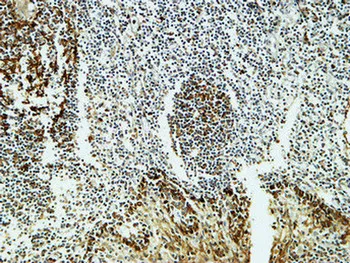

FOXP1 Rabbit Polyclonal Antibody

Cat: APRab11113

Size1:50μl Price1:$118

Size2:100μl Price2:$220

Size3:500μl Price3:$980